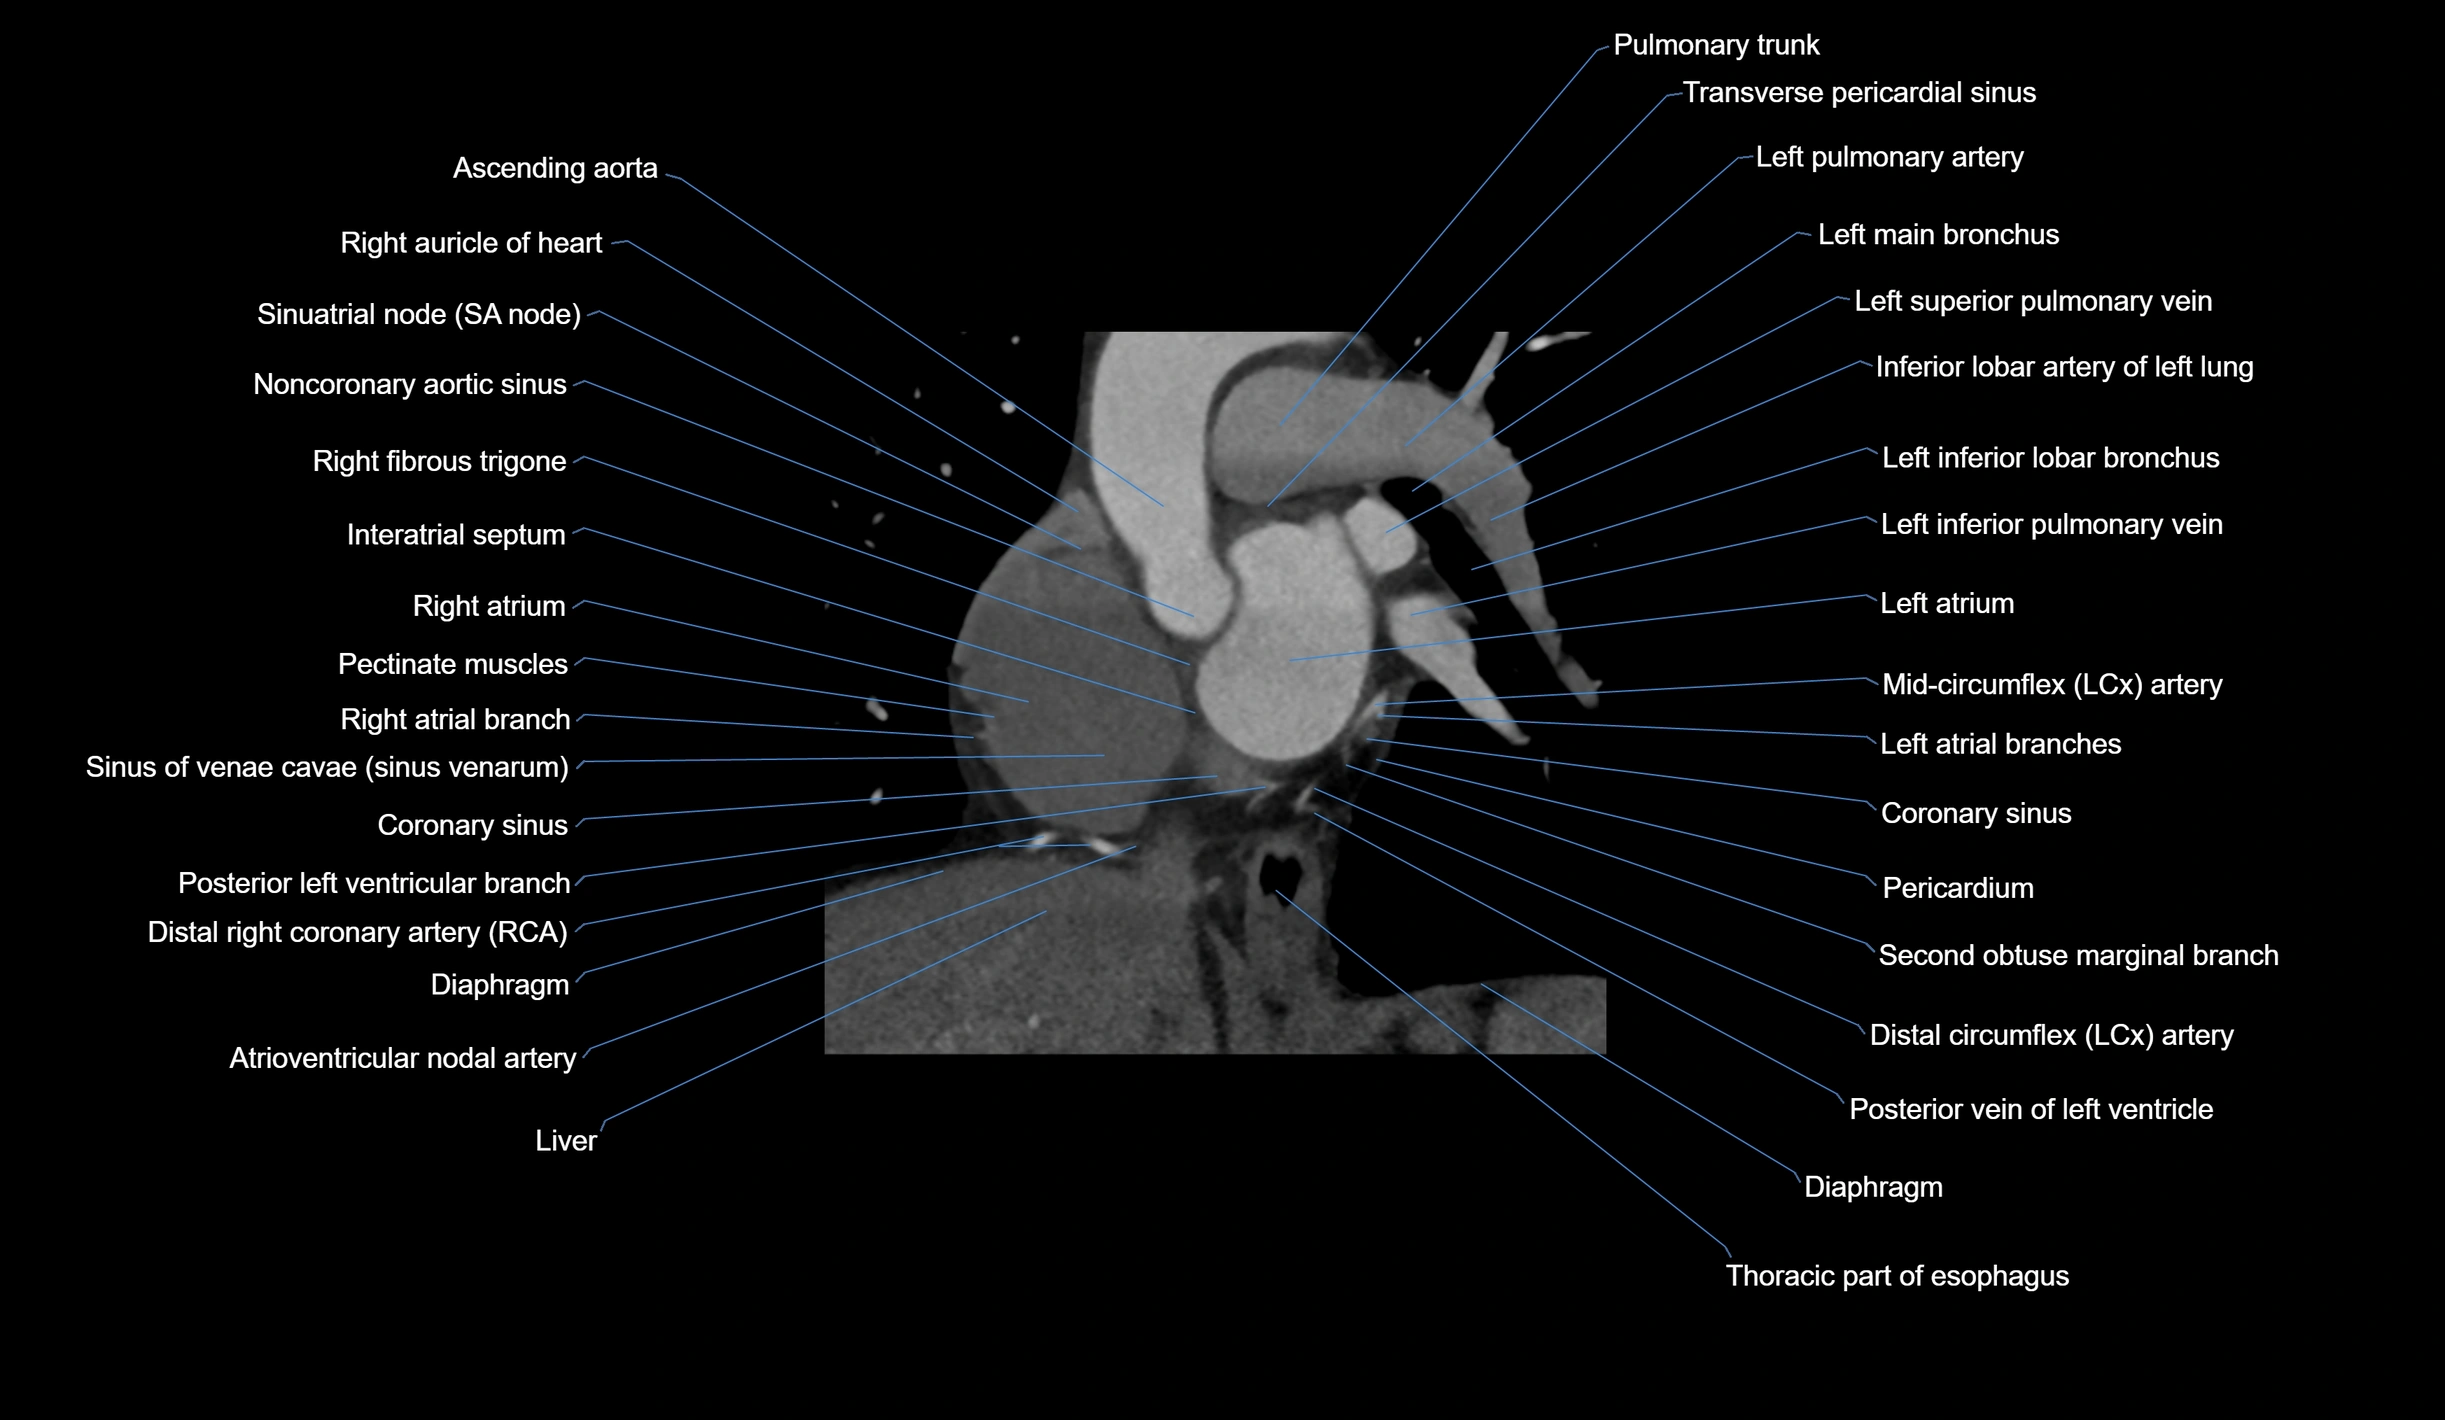

- Ascending aorta

- Right auricle of heart

- Sinoatrial node (SA node)

- Noncoronary aortic sinus

- Right fibrous trigone

- Interatrial septum

- Right atrium

- Pectinate muscles

- Sinus of venae cavae (sinus venarum)

- Coronary sinus

- Posterior vein of left ventricle

- Pulmonary trunk

- Left pulmonary artery

- Left main bronchus

- Left superior pulmonary vein

- Left atrium

- Left inferior pulmonary vein

- Left inferior lobar bronchus

- Transverse pericardial sinus

- Diaphragm

- Pericardium